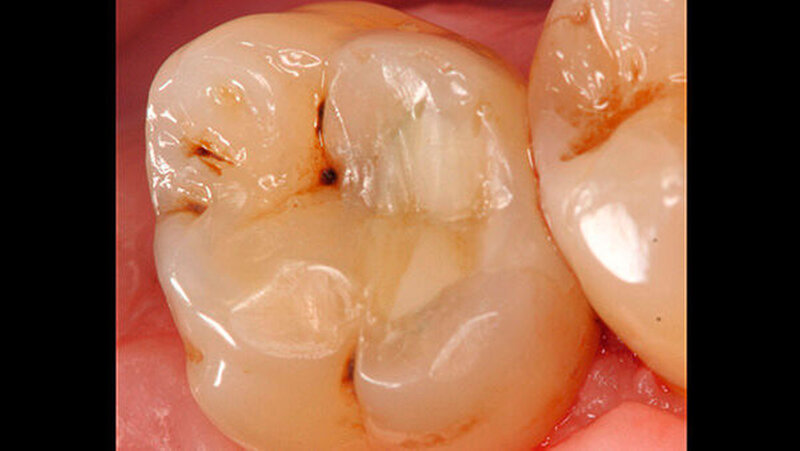

Anschließend erfolgte die Kariesexkavation mit Rosenbohrern unter optischer Kontrolle mit einem OP-Mikroskop. Die Kavität wurde im Verlauf der Exkavation mehrmals mittels FACE (fluoreszenzgestützter Kariesexkavation, SIROinspect, Sirona) auf Residualkaries überprüft [Buchalla W et al., 2013].

Bei der vollständigen Kariesentfernung kam es nicht zu einer Freilegung der Pulpa (Abbildung 3). Anschließend wurde eine Metallmatrize (HaweTofflemire Matrize, Kerr Dental) angelegt und verkeilt. Die Kavität wurde gereinigt und getrocknet.